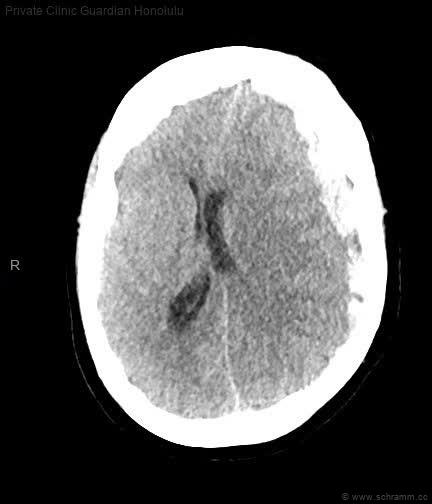

In der folgenden craniellen Computertomographie (CCT) findet sich ein(e):

Das subdurale Hämatom zeigt sich charakteristisch als zum Hirngewebe konkav verlaufende intrakranielle Blutung. Es handelt es sich um eine Blutung zwischen Dura mater und Arachnoidea. Pathophysiologisches Korrelat des Subduralhämatoms ist meist ein Riss der Brückenvenen, die die oberflächlichen Hirnvenen zu den Sinus durae matris drainieren. Bei dem akuten subduralen Hämatom kommt es innerhalb von wenigen Stunden zu einer Einblutung in den Subduralraum mit zunehmendem Druck auf das umgebende Gehirn und entsprechender neurologischer Symptomatik. Therapeutisch bleibt hier nur die sofortige Operation.